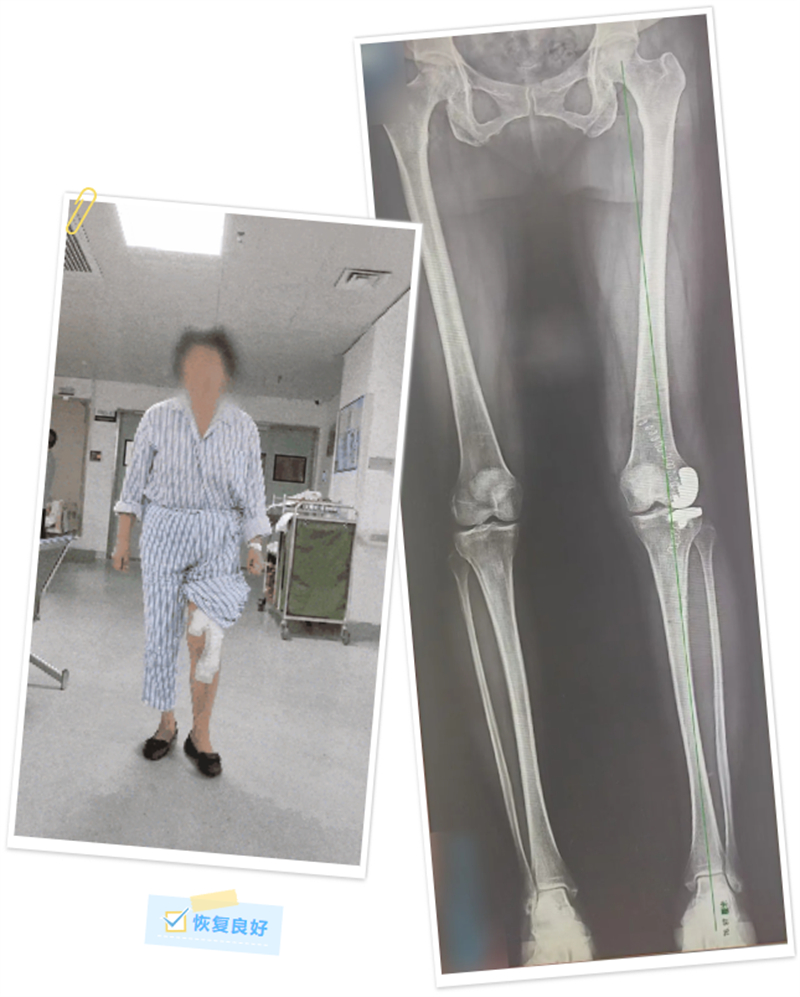

術前,手術團隊將患者的下肢CT數據錄入機器人系統后,運用計算機對假體的位置及型號參數進行了詳細的規劃和模擬,術中再次對患者的下肢力線及軟組織張力進行了實時校對和調整。在機械臂連接的專用工具輔助下,最終成功將假體植入,并獲得了較好的軟組織張力平衡和活動度,同時糾正了患者的下肢力線。

術后,覃女士恢復良好,還送來了寫著“醫術精湛、醫德高尚”的錦旗表示感謝。